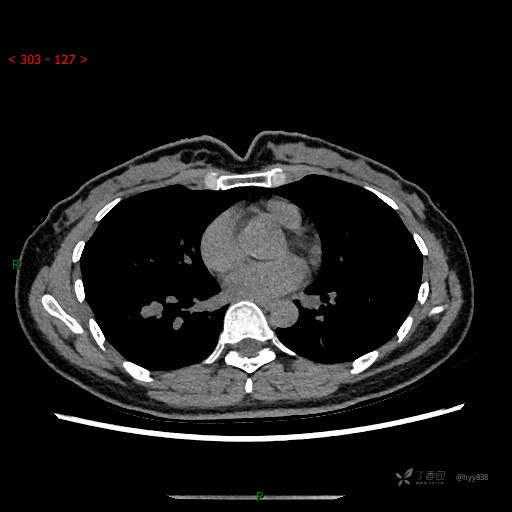

胸部CT平扫